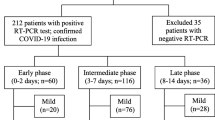

Phases of COVID-19 pneumonia

Autoptic specimens of deceased patients with COVID-19 pneumonia revealed the presence of diffuse alveolar damage (DAD) at different stages as the major pathologic finding [15,16,17]. DAD tends to evolve through three progressive phases [18]. The first phase is the exudative phase, characterized by capillary congestion and edema, alveolar haemorrhage, and hyaline membrane formation. Approximately 7 days after the start of injury, a proliferative phase occurs, consisting of fibroblast proliferation within the interstitium and alveoli, thickening of the interlobular septa, type 2 pneumocyte hyperplasia, parenchymal remodelling and appearance of organizing pneumonia (OP) foci. Finally, after 2 weeks, the fibrotic phase may develop, with collagen deposition and progressive fibrotic changes [18]. Each phase is associated with different imaging findings, which correlate well with the progression of DAD over time [19]. These phases correspond to the evolution of imaging features in COVID-19 pneumonia.

Pan et al. identified on HRCT four consecutive temporal stages in patients who recovered from COVID-19 pneumonia: the early stage (0–4 days from the onset of symptoms), the progressive stage (5–8 days), the peak stage (9–13 days), and the absorption stage (≥ 14 days) [20]. In another study by Wang et al. a similar time course was described, even though a delayed dissipation phase was noticed, possibly due to the inclusion of more severe cases [21]. Comparable evolution of radiological findings has also been reported on CXR [22, 23].